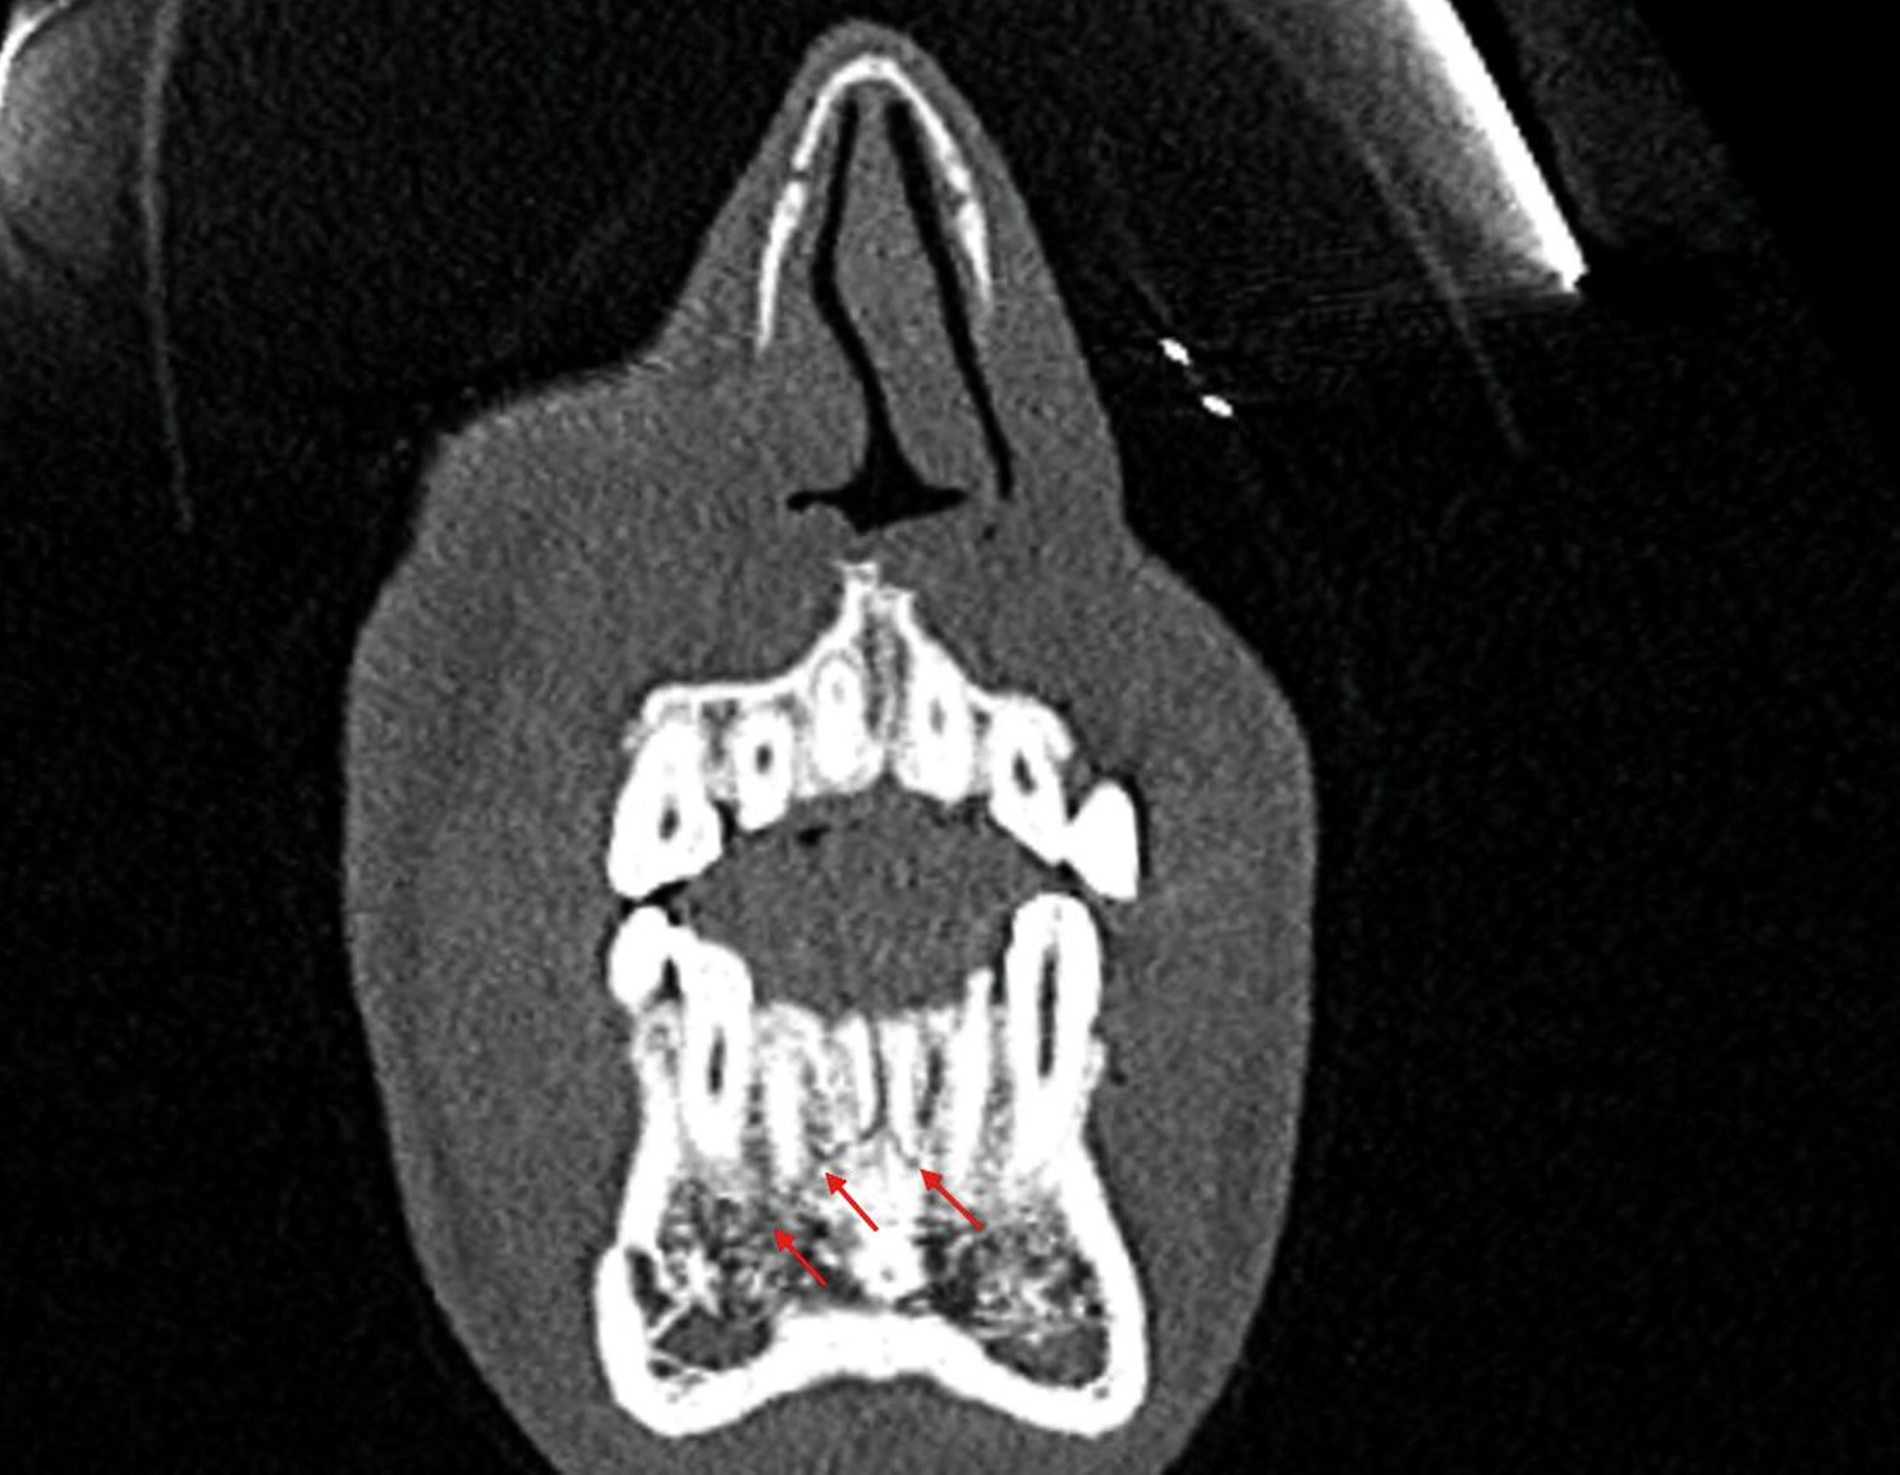

Nach der Aufklärung und der Extraktion des mobilen Zahnfragments Regio 24 wurde der Patient an die Klinik für Mund-, Kiefer- und Gesichtschirurgie der Charité überwiesen. Dort wurde noch am selben Tag eine Computertomografie (CT) des Mittelgesichts angefertigt (Abbildung 6), die die Verdachtsdiagnose bestätigte.

Laut dem radiologischen Befundbericht lag „eine nicht wesentlich dislozierte, paramediane Unterkieferfraktur rechts“ vor. Die Reposition und die Fixierung der Mandibula erfolgten am darauffolgenden Tag mithilfe von zwei Miniosteosyntheseplatten durch einen vestibulären Zugang in Intubationsnarkose. Die radiologische Kontrolle zwei Tage nach der operativen Versorgung ergab eine adäquate Stabilisierung der Fraktur durch die beiden Miniosteosyntheseplatten (Abbildung 7).